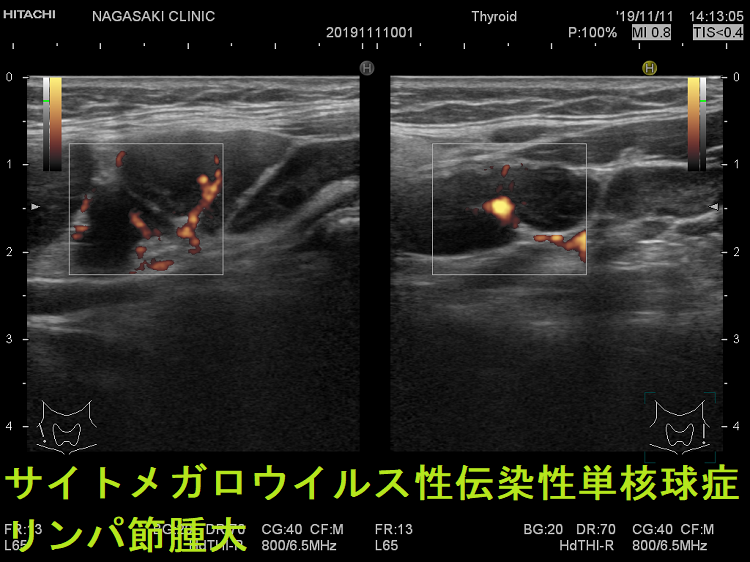

- 痛みを伴う著明な後頸部リンパ節腫脹は1〜2週頃がピークで、耳下腺の下、外側頚部まで累々と広がり、全身のリンパ節も腫大します。

- 亜急性甲状腺炎と鑑別を要する伝染性単核球症を発症